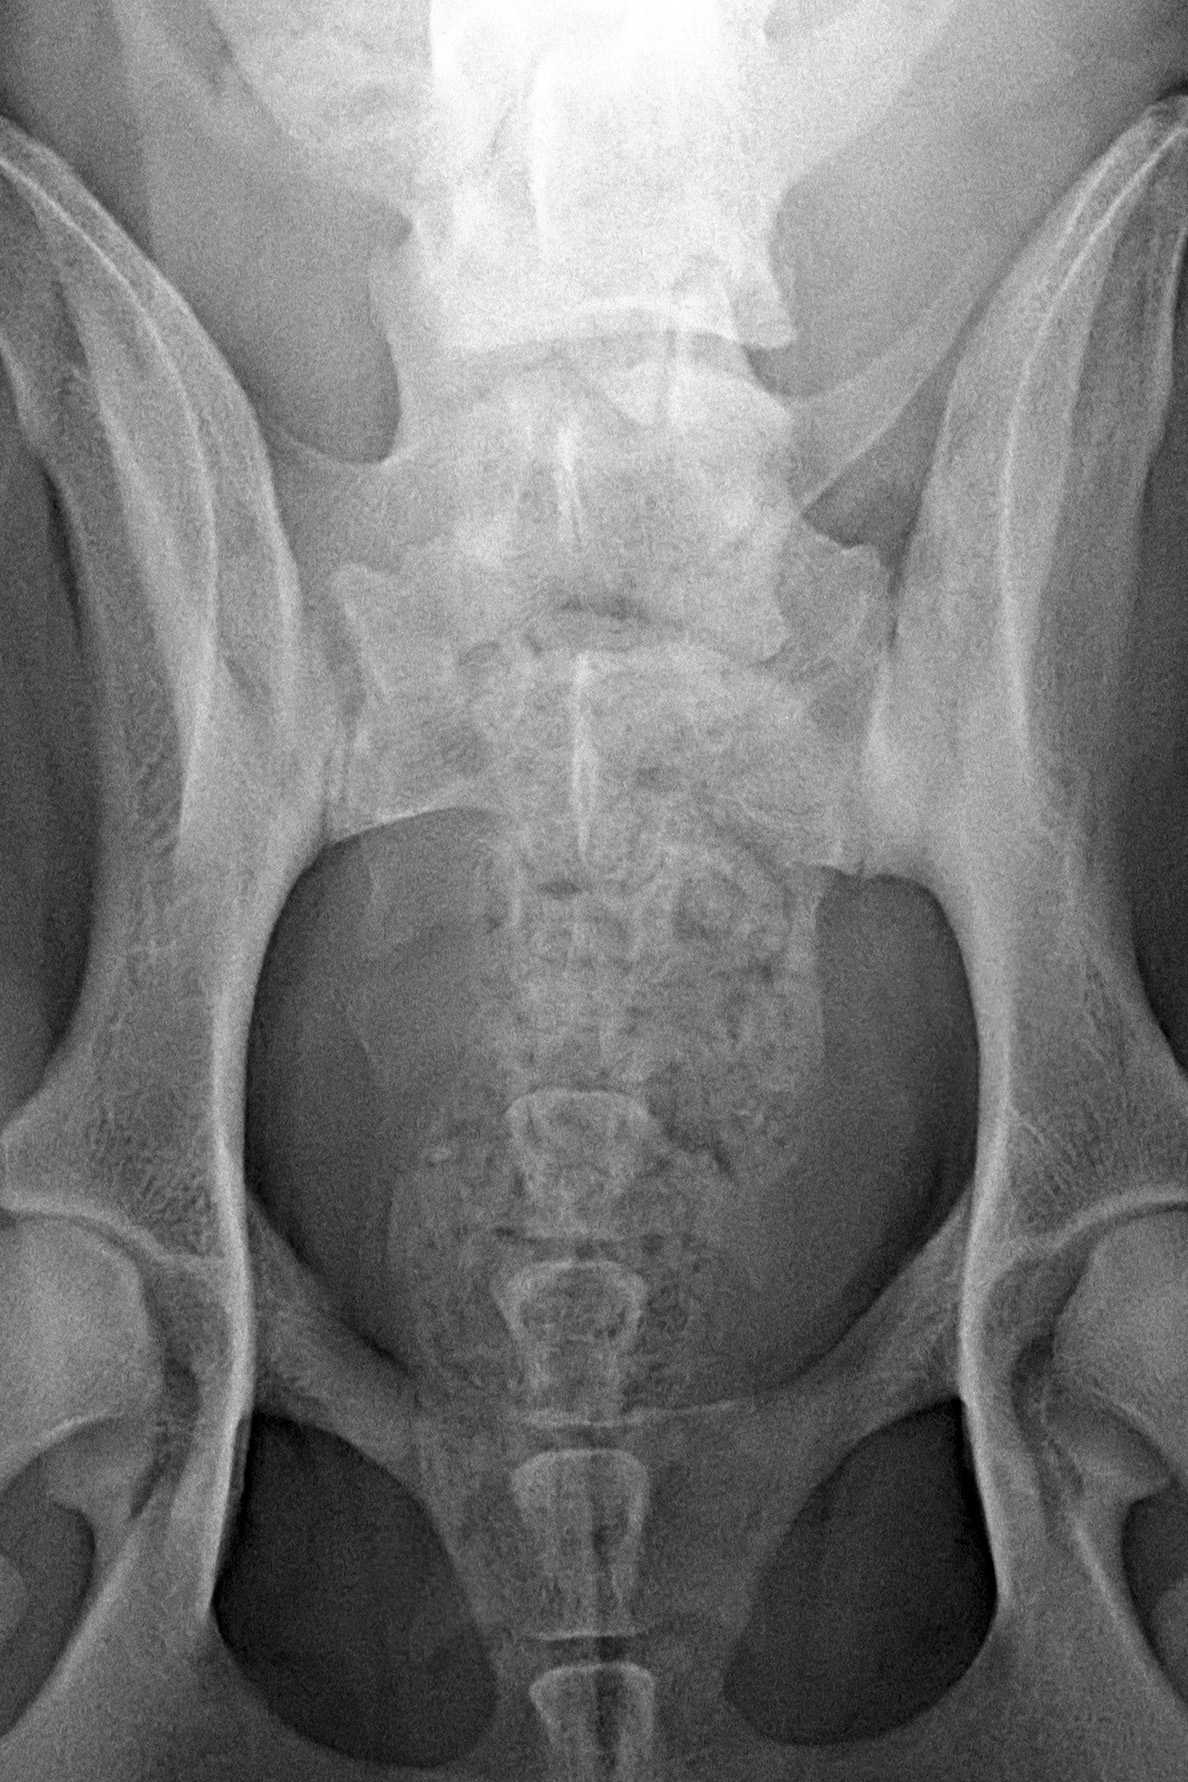

(4) 7 měsíců VD 2

(4) typ 3 po korekci polohy pánve 2